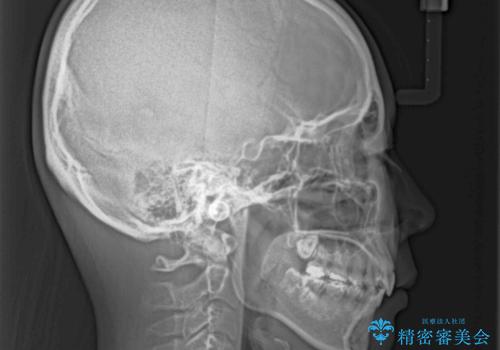

治療後には口が閉じやすくなり、患者様には大変満足していただきました。